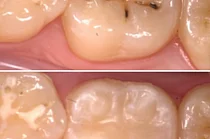

Герметизация фиссур – современный и эффективный метод профилактики кариеса. Она проводится путём запечатывания фиссур герметиком – специальным пломбировочным материалом - без нарушения целостности эмали. Частички еды застревают в фиссурах, в них поселяются бактерии, что очень быстро вызывает кариес. Герметики предотвращают застревание еды в фиссурах и питают эмаль, помогая ей сформироваться здоровой.

• После того, как поверхность высыхает, на абсолютно чистую фиссуру наносится материал для запечатывания (герметик) и высушивается до затвердевания с помощью специальной светополимерной лампы.